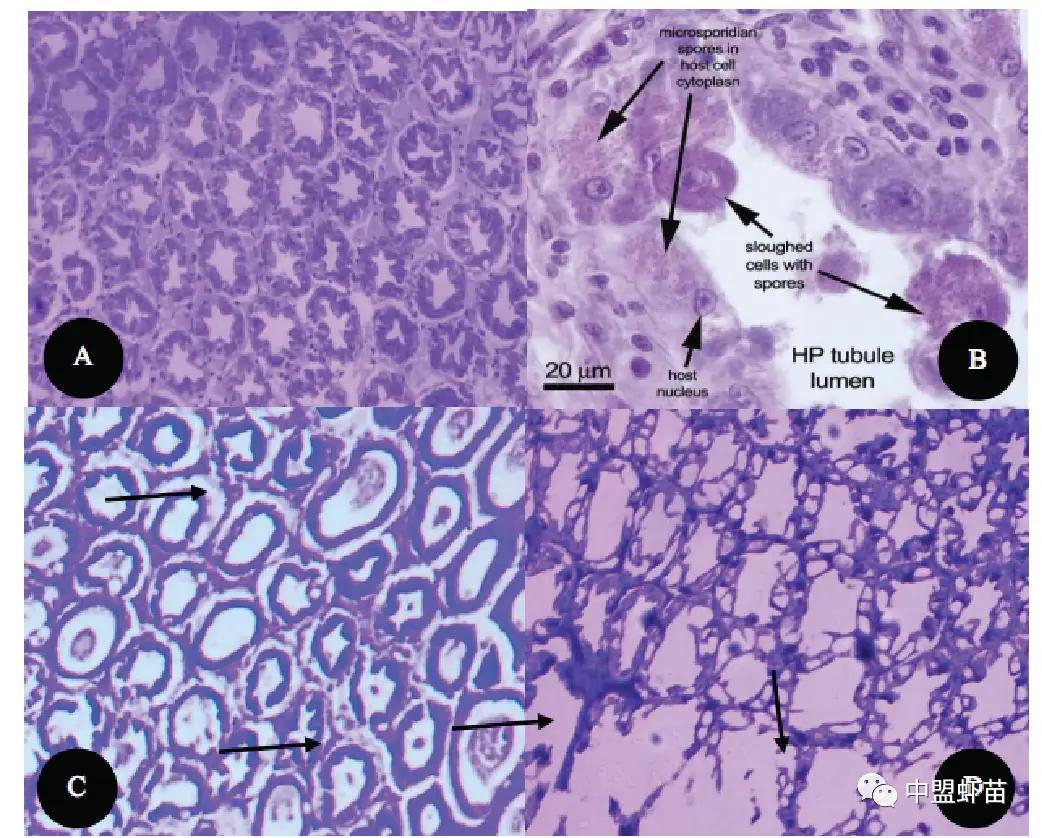

肝胰腺 (HP) 组织H&E染色切片中的ATM合成步骤与真正的Gregarine寄生虫进行比较。

健康虾肝样本 (A) 和感染 EHP 的虾样本 (B)

A.肝胰腺结构正常;B. 孢子出现和肝胰腺脱落;C. 肝胰管解剖;D. 严重的细胞损伤